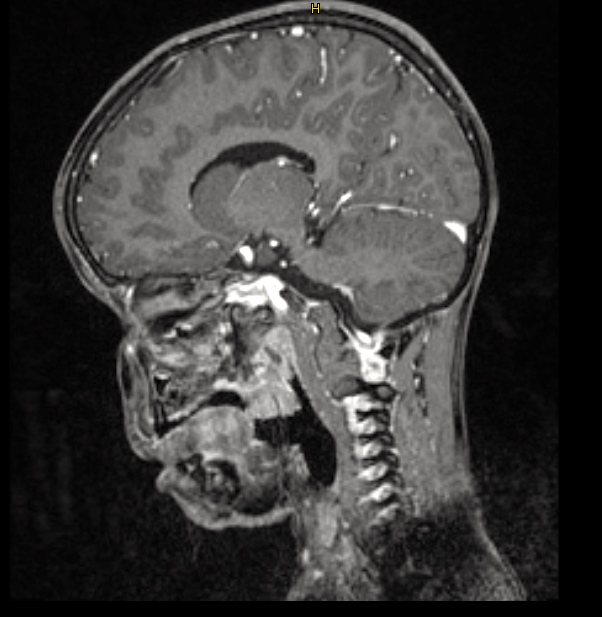

Somit hat man ein MRT der Wirbelsäule gemacht, allerdings mit keinem ins Muster passenden Ergebnis.